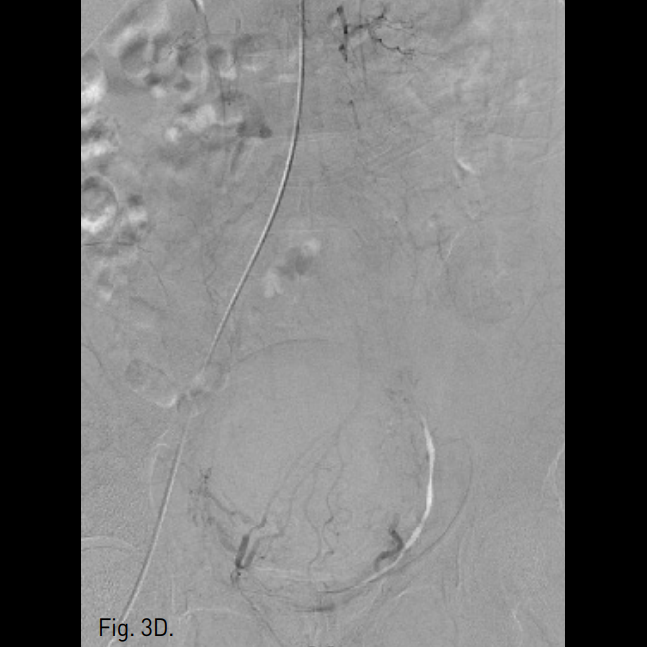

Fig. 3

C, D. After uterine ar tery embolization, hypertrophied uterine artery could not be seen.